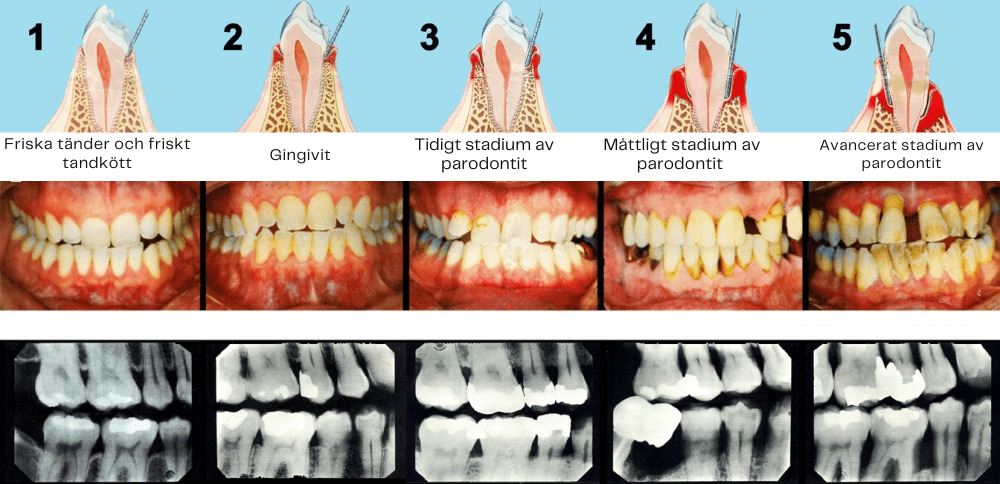

Om du svarade "ja" på någon av dessa frågor lider du av tillbakadraget tandkött, även känt som tandköttsförlust, ett vanligt oralt problem som kännetecknas av den gradvisa förlusten av tandköttsvävnad, vilket lämnar tandrötterna exponerade.

Tandköttsförlust uppstår när tandköttsvävnaden drar sig tillbaka eller slits bort från tänderna, vilket blottar de känsliga tandrötterna. Detta tillstånd är mer än bara ett kosmetiskt problem; det gör tänderna sårbara för karies, infektioner och till och med tandförlust om det inte behandlas. När tandköttet drar sig tillbaka bildas "fickor" eller mellanrum vid tandköttslinjen där bakterier samlas, vilket gör att recessionen förvärras över tid.